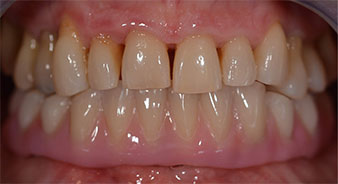

Im Anschluss erfolgt die Abformung und Bissnahme, sodass die Zahntechniker umgehend mit der Anfertigung der provisorischen Arbeit beginnen können. Diese wird im Anschluss am gleichen Tag eingeschraubt (Abb. 17 und 18).

Implantate

Abb. 17

Abb. 18

Nach der Zeit, die für die Osseointegration benötigt wird, kann die endgültige Abformung der Implantate erfolgen und entsprechend die endgültige Arbeit angefertigt werden (Abb. 19 und 20). Hier können Behandler und Patient gemeinsam entscheiden, ob diese eine Keramik- oder Kunststoffverblendung, ein Zirkon- oder Metallgerüst bekommen soll. Im vorliegenden Fall hat sich das Team um Dr. Pascu, aufgrund der unklaren Prognose der Oberkieferbezahnung und des elongierten Zahnes 24, für eine Kunststoffverblendung entschieden. Diese ist im Allgemeinen wesentlich einfacher umzustellen und der neuen Situation im Oberkiefer anzupassen.